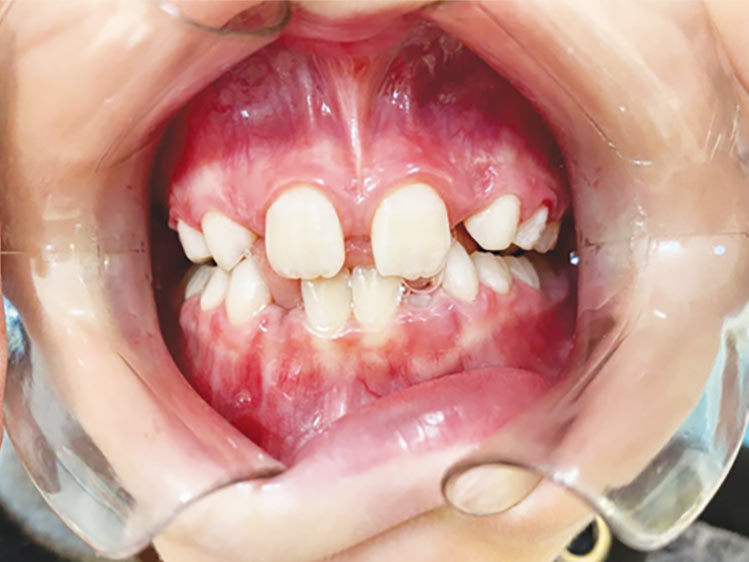

É necessário fazer uma avaliação clínica e radiográfica criteriosa da oclusão do paciente.

Se algo estiver fora da normalidade, o problema poderá ser interceptado e corrigido prontamente, evitando longos tratamentos ortodônticos no futuro.